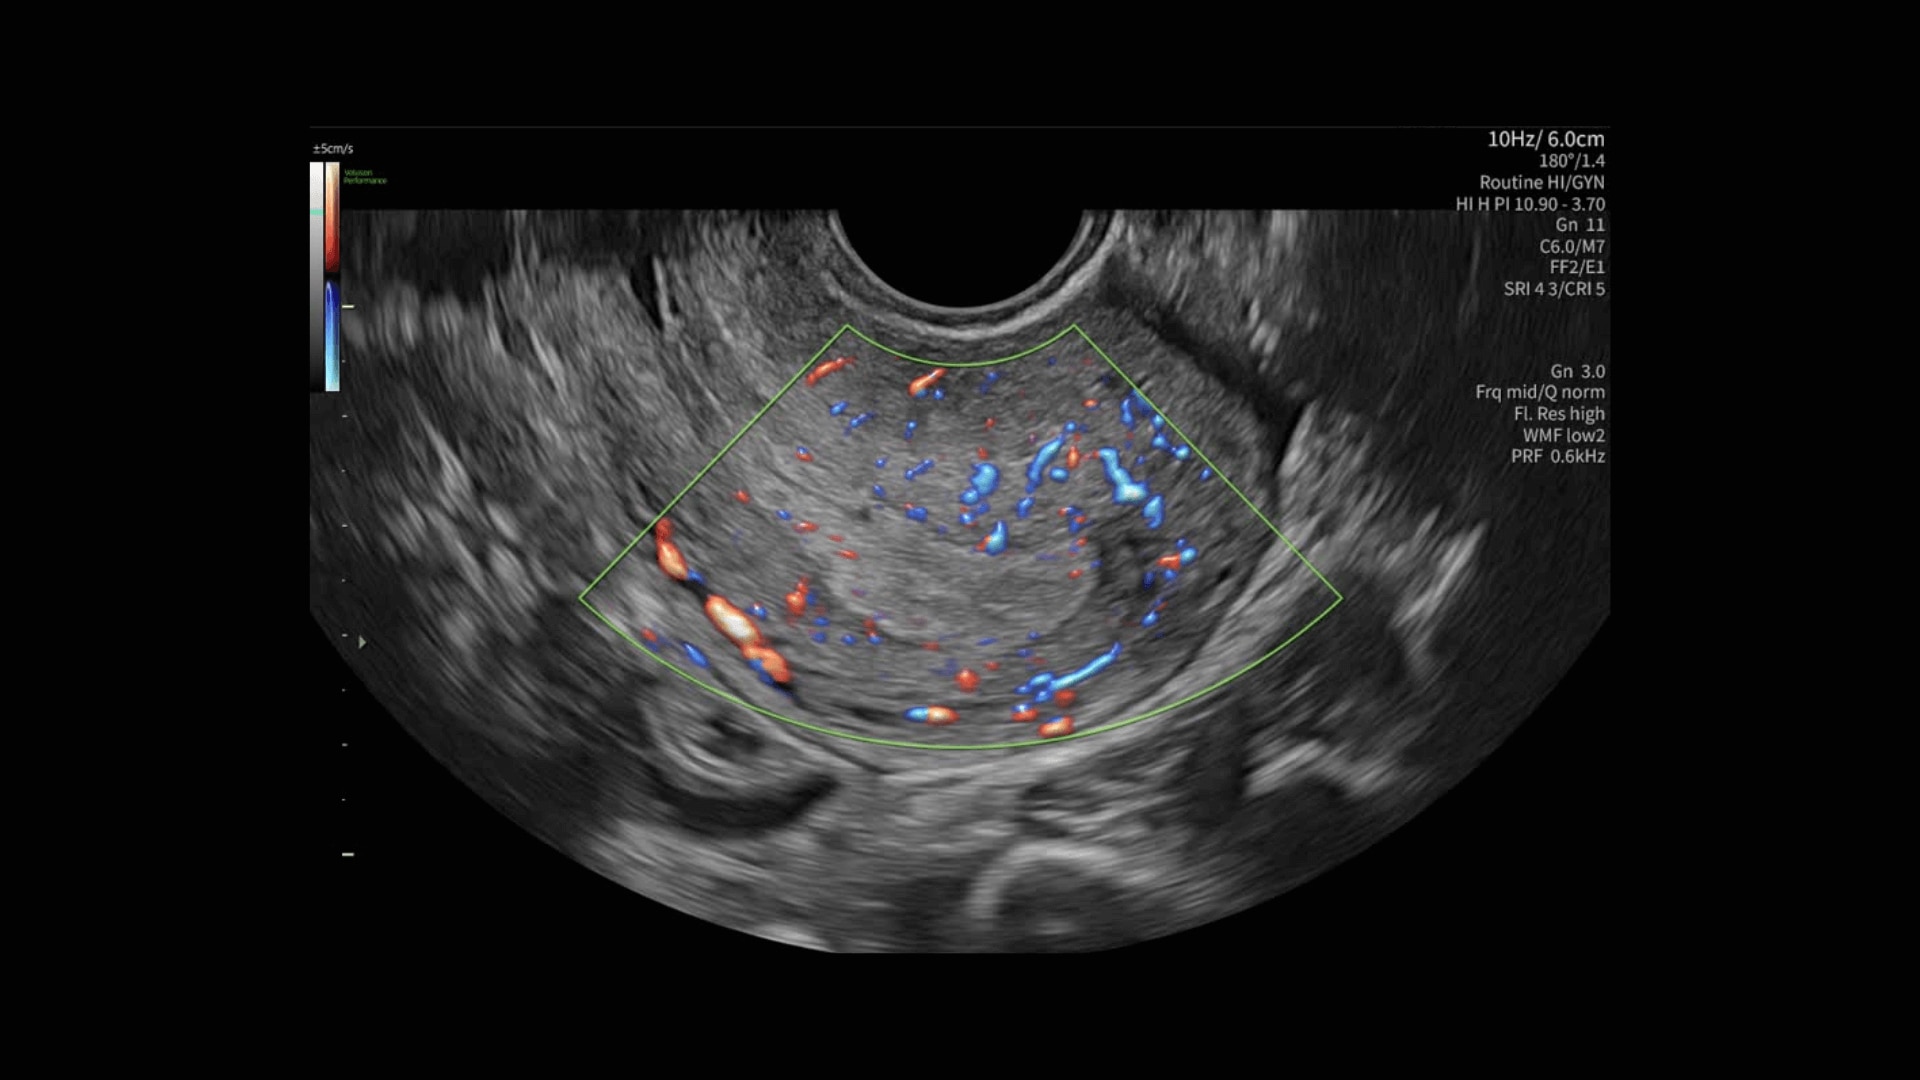

Radiantflow™

Fast, easy 3D-like blood flow visualization

Radiantflow delivers exceptionally sensitive, next level color Doppler for easy fast visualization of blood flow revealing even the tiniest vessels.